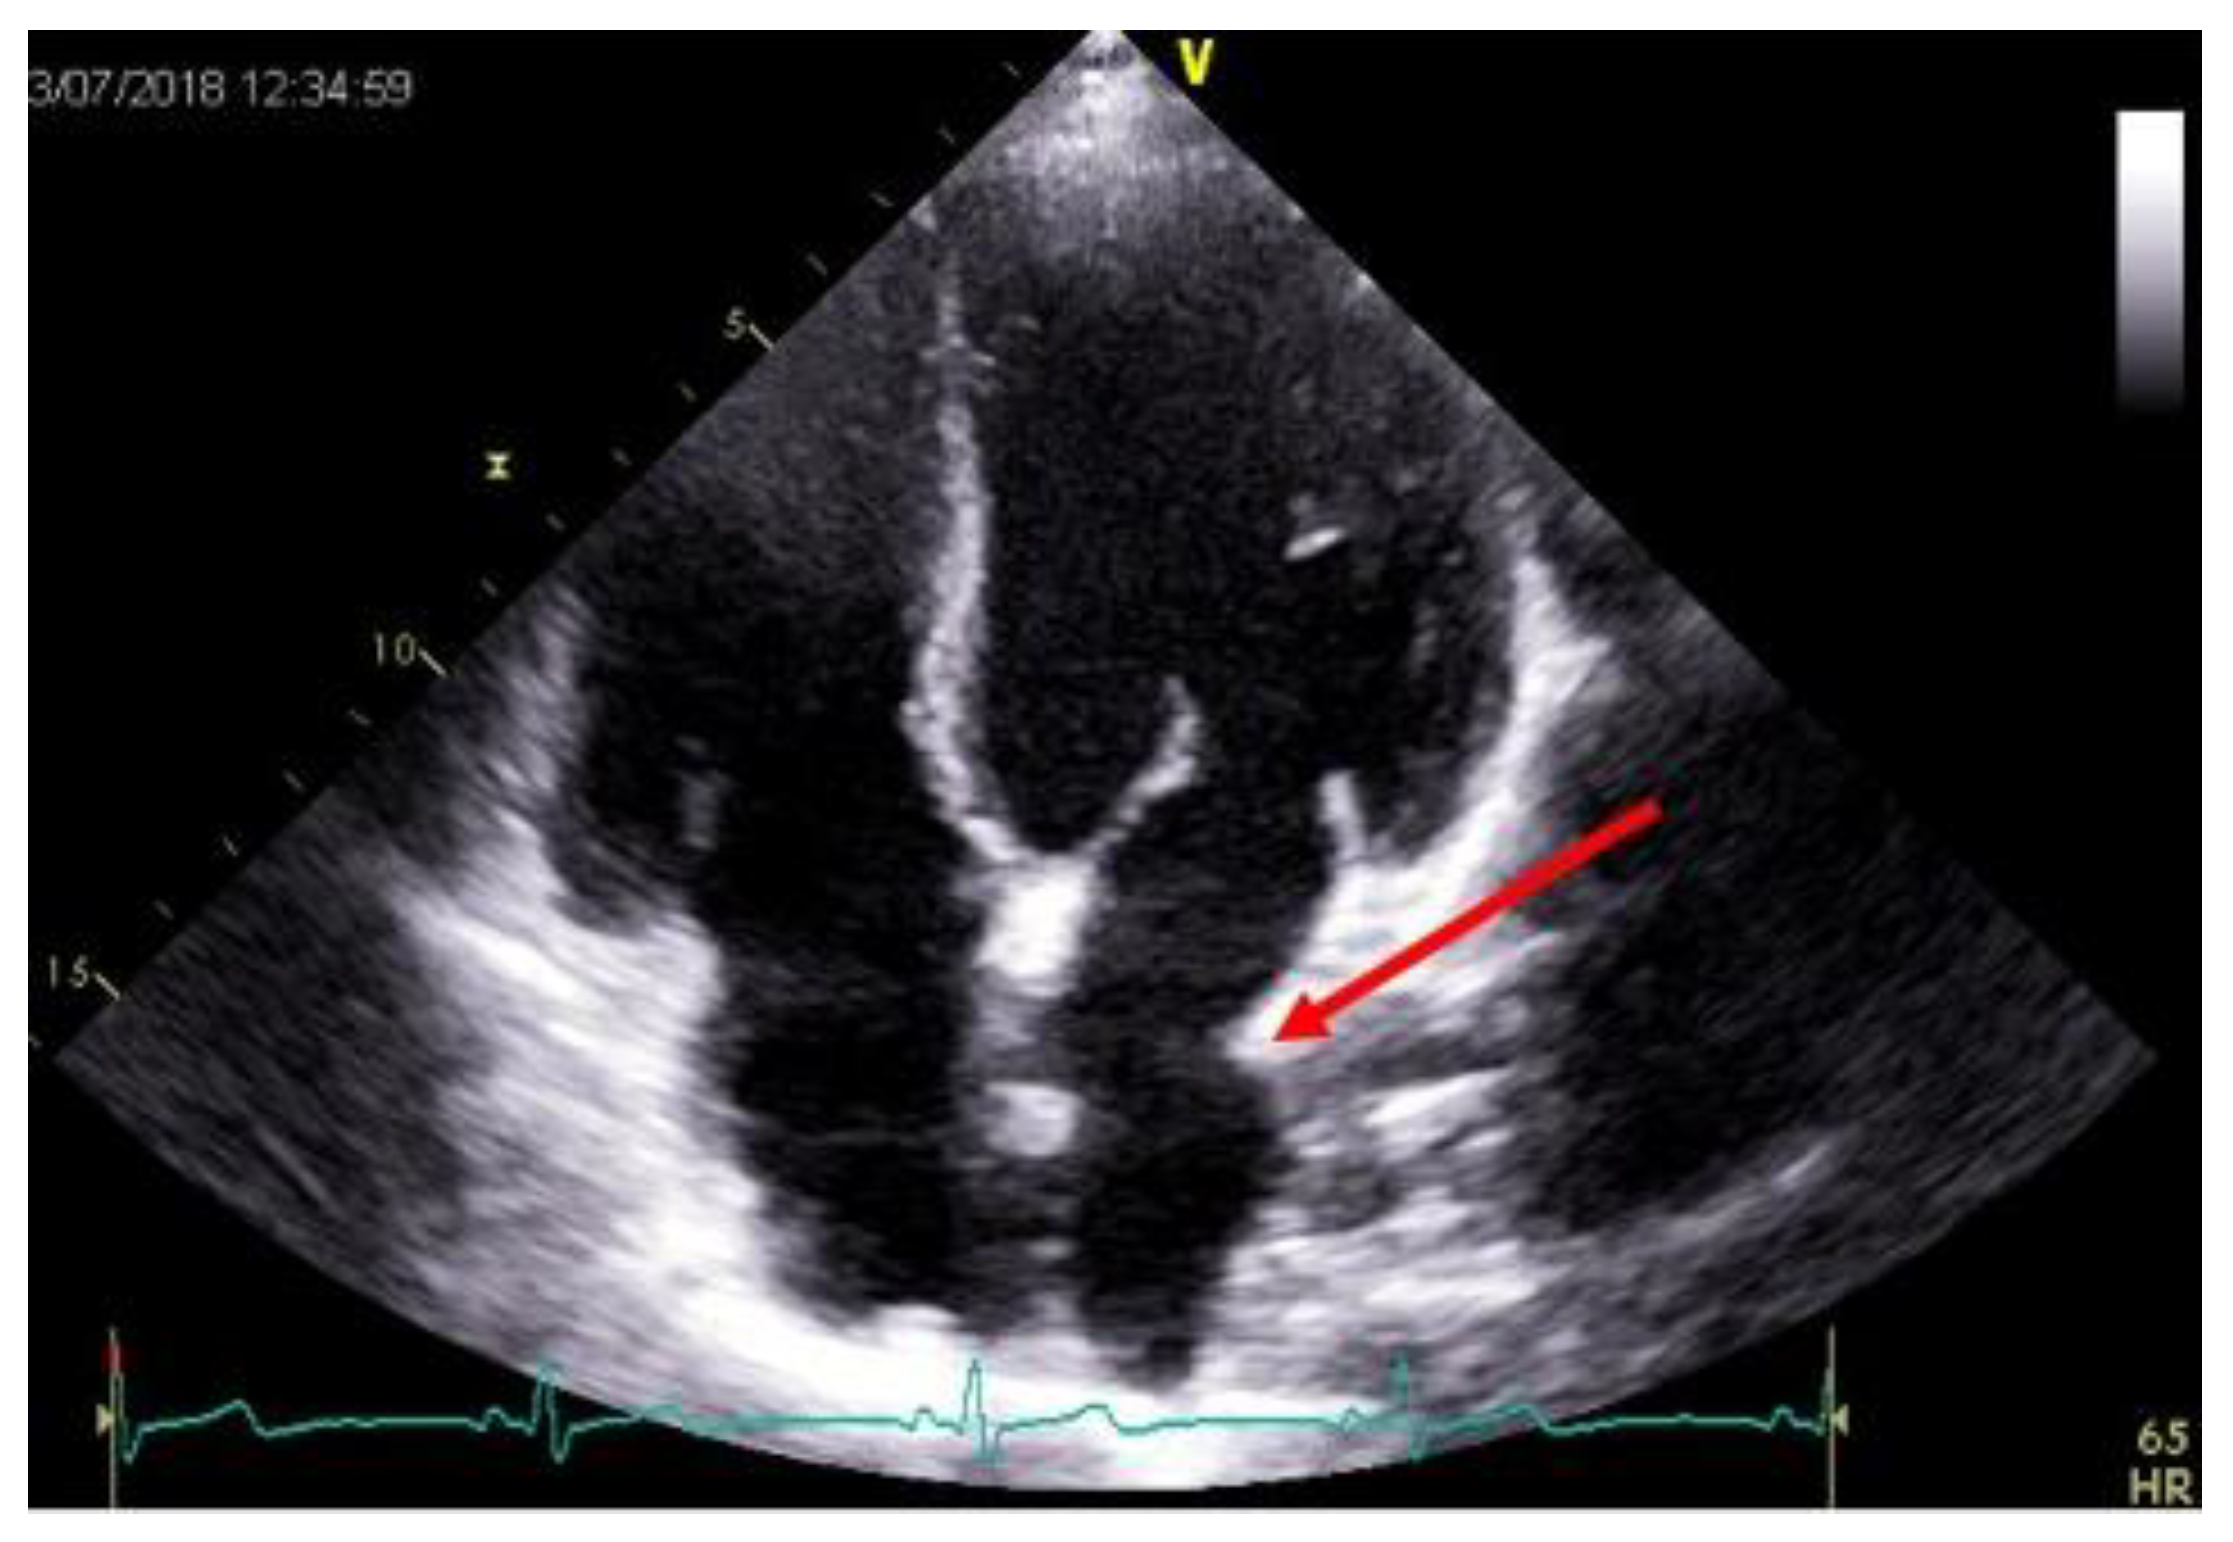

2.5. Pericardium